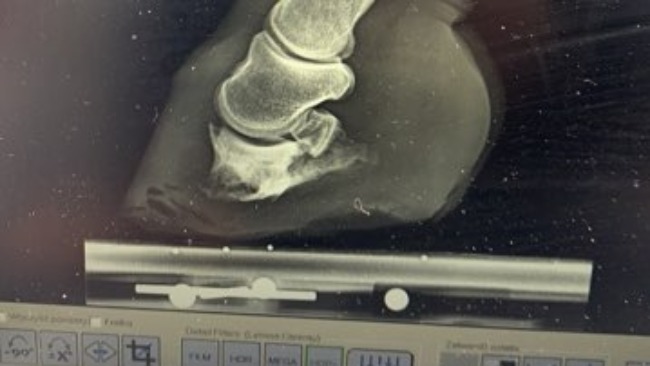

I przez to ma duży ubytek kości kopytowej,Co nie umożliwiło jej to komfortowego chodzenia,każdy krok to był krok strasznego bólu. Kilku weterynarzy chciało ja uspac,ja nie potrafiłam podjąć takiej decyzji. I walczyłam o Birke z całych sił,udało się I było warto. Przyjechała do nas pani doktor z Bydgoszczy razem ze swoim kowalem i zbadali Birke. Zrobili RTG i okazało się że jak Birka będzie systematycznie werkowana przez dobrego kowala to będzie chodzić,ba lepiej nawet brykac będzie . Jest szczęśliwa nic już jej nie boli .

Kochani musimy Birke werkowac co 4tygodnie,Ale przed werkowaniem weterynarz musi robić RTG bez tego Birka nie może być werkowana.